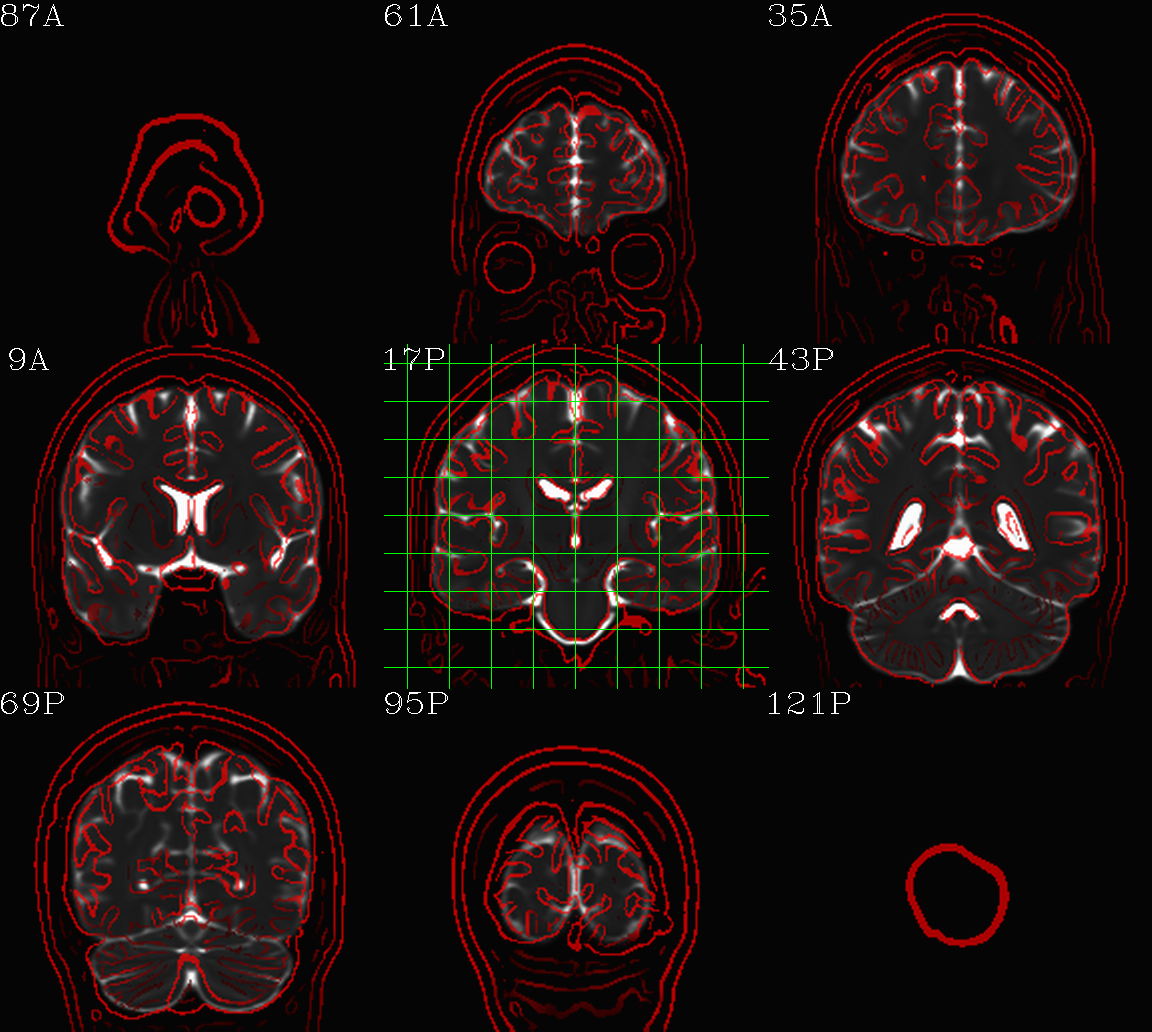

t2w_qc00_fin.*.png |

autoimages, multiple slices per 3D volume, with single scaling across the volume, showing the final axialized volume; grid slice lines are also shown in the central volume, for visual reference of major plane lines. |

t2w_qc01_ref_u_inp.*.png |

autoimages, multiple slices per 3D volume; the image is in

the space of the |